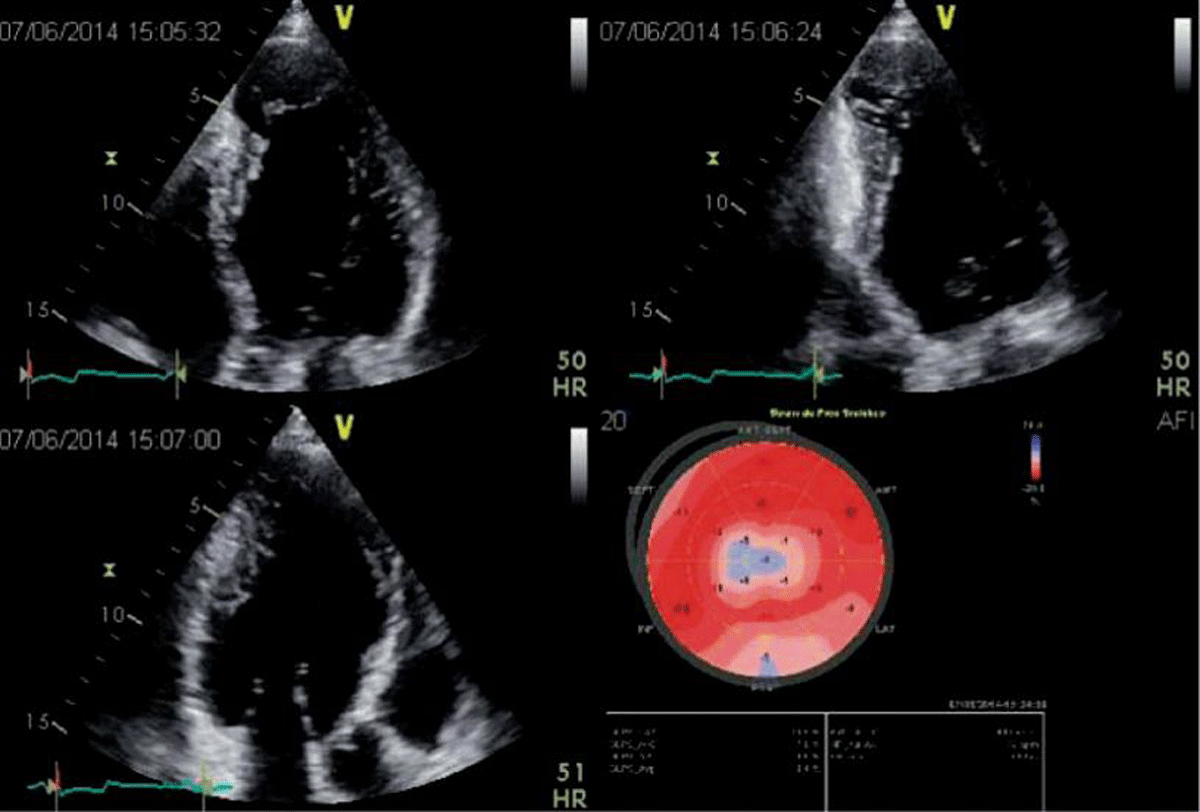

3.3.2 Apical aneurysm and thrombi

Apical aneurysms are a hallmark of Chagas disease, so the presence of apical aneurysm should raise suspicion of ChCM [283139]. These aneurysms are characterized using 2D echo as the presence of a deformity outside the endocardial border, persisting in systole and diastole. In general, these aneurysms are small, have a narrow neck, and may contain thrombi (Figure 3). Particular attention should be paid to spontaneous echo contrast and the presence of thrombus in ventricular chambers, especially associated with an aneurysm, as thrombi are important risk factors for systemic embolisms [4041]. Importantly, these aneurysms are not always seen in the traditional apical views, and may be missed if a comprehensive echo is not performed. Unconventional views, especially a modified apical 2-chamber view, with posterior angulation of the transducer, are necessary to visualize the apical aneurysm and its associated thrombus.

Figure 3

2D apical 4, 2 and 3-chamber views in a patient with Chagas disease and a typical aneurysm. In the 2-chamber view, a basal inferior aneurysm is also present. Longitudinal strain is abnormal in the apex, as well as on the basal inferior wall. Image: Marcia Barbosa. Reproduced with permission of the photographer.

The prevalence of aneurysms varies widely from study to study because of the heterogeneity of the population analyzed and the accuracy of the imaging method used for diagnosis. Nevertheless, LV apical abnormalities have a low prevalence in those with normal ECG findings but increase to 24% in those with an abnormal ECG [322].